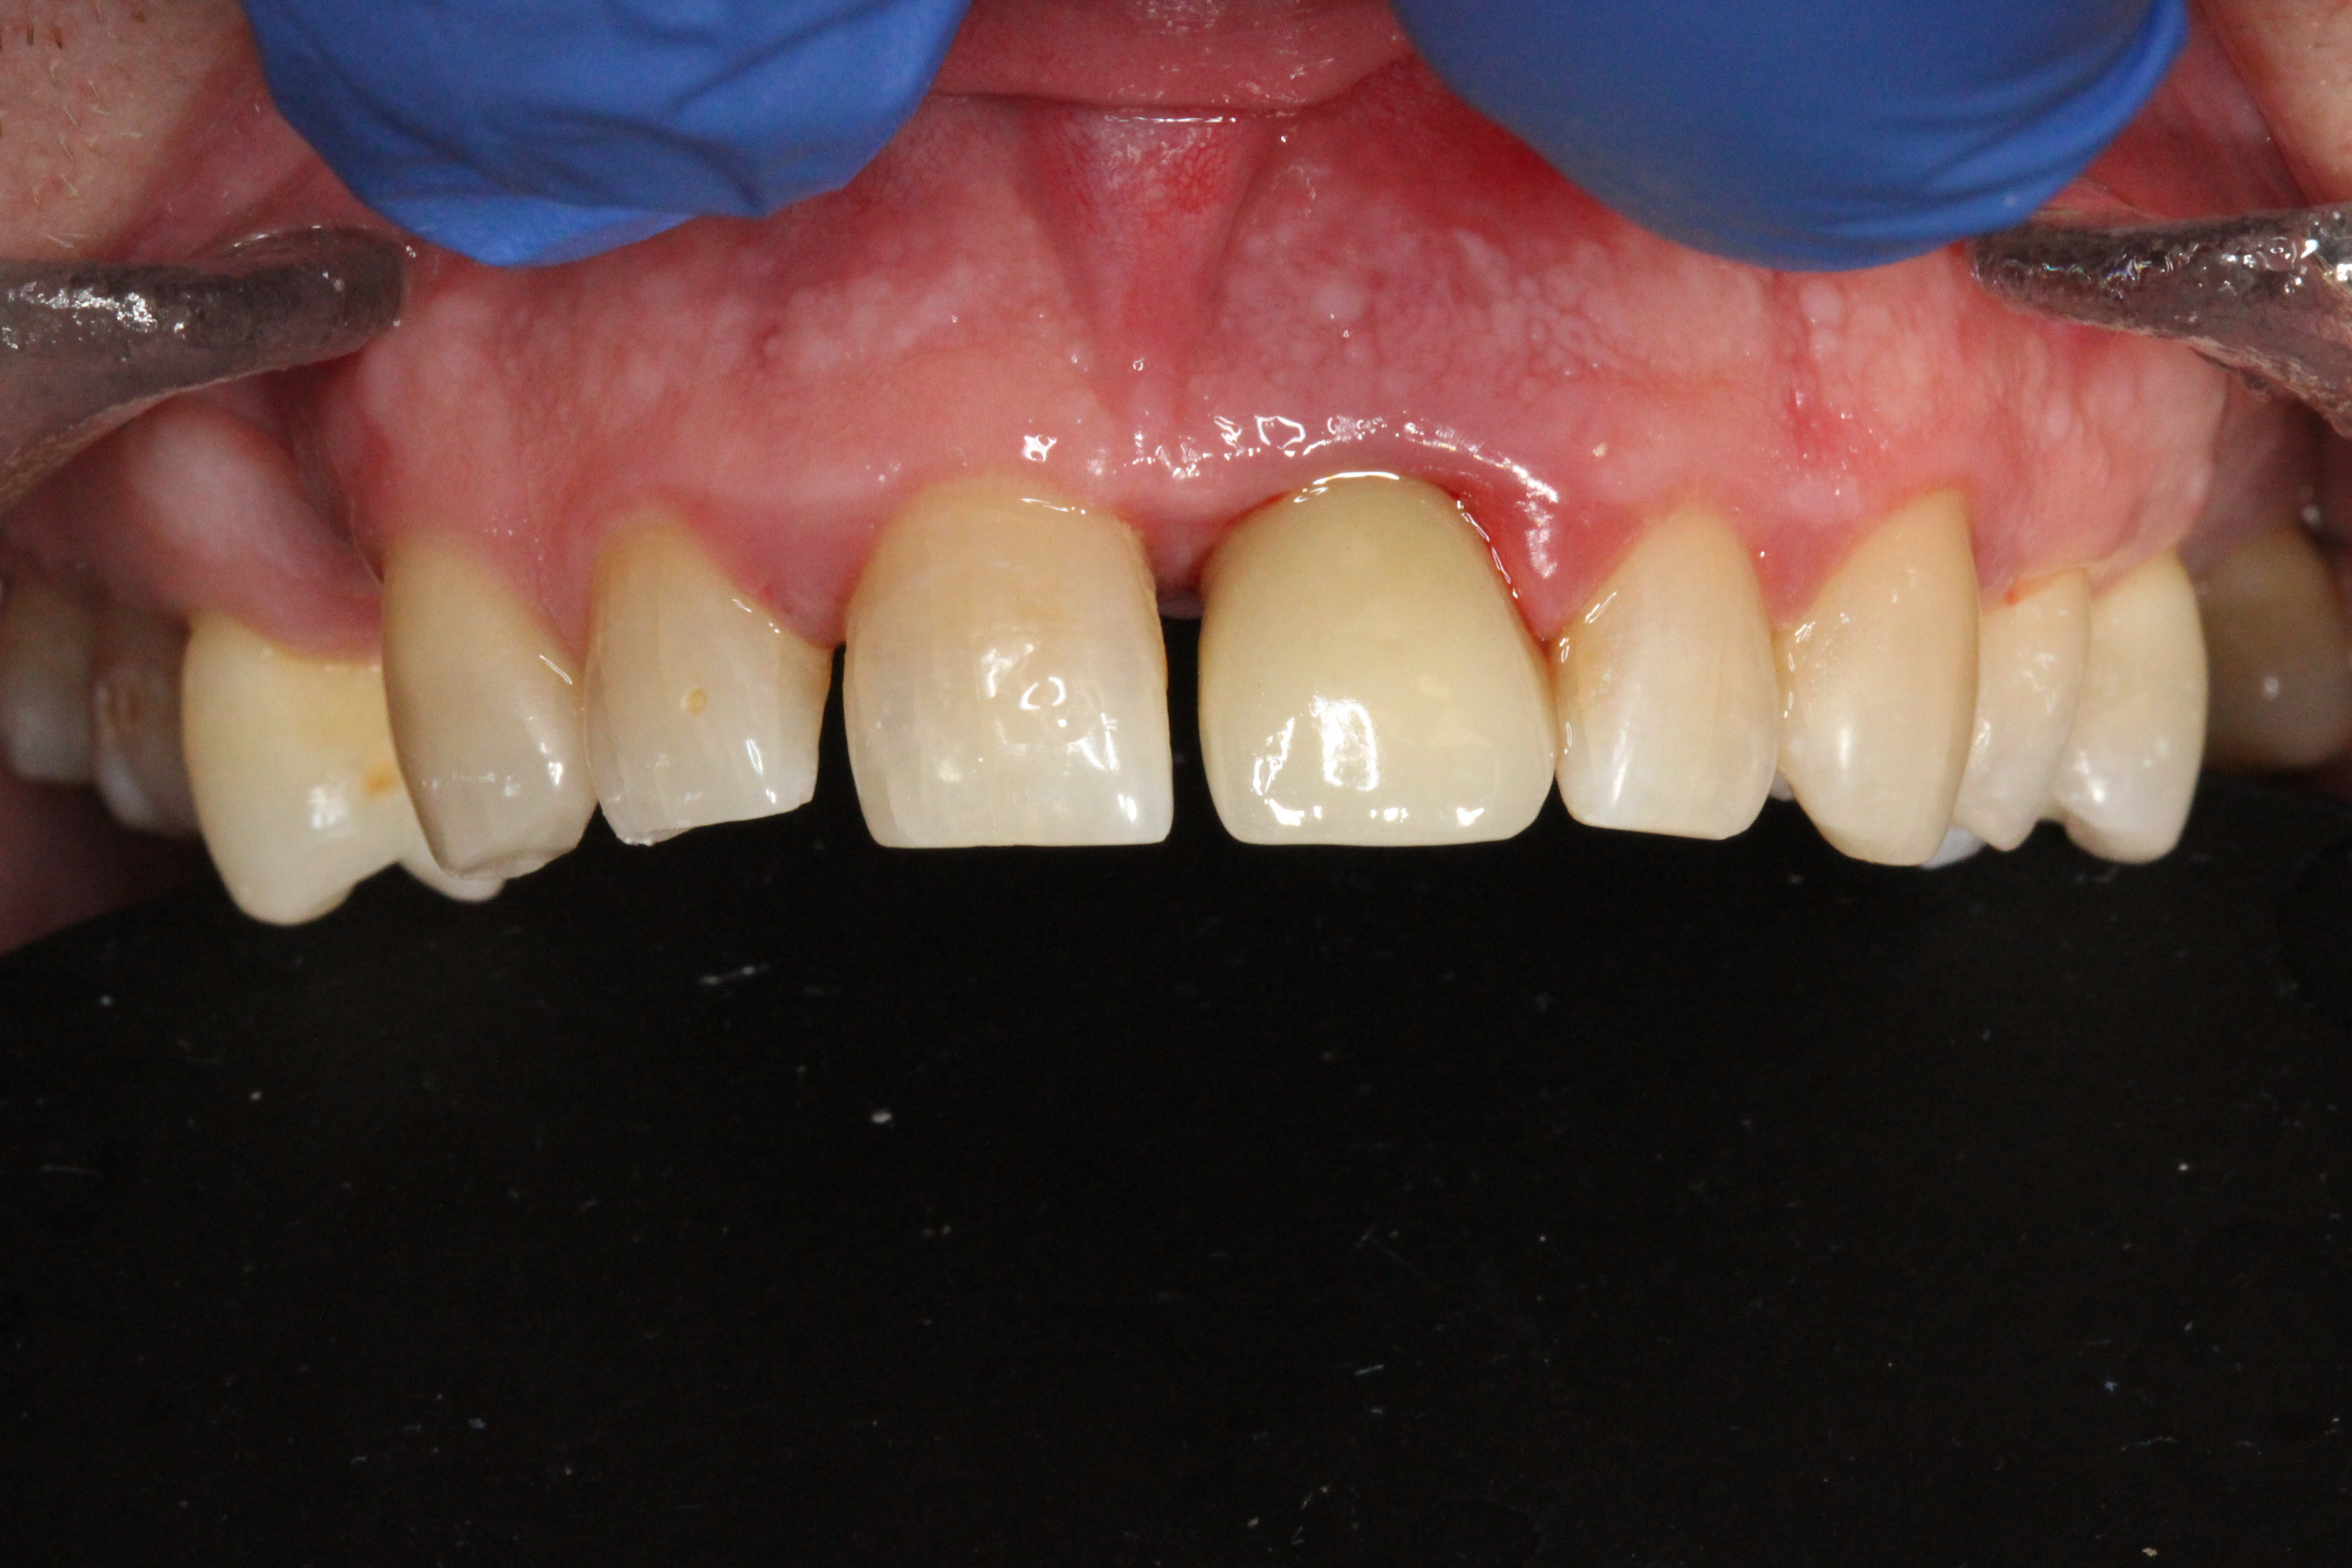

The prosthetic phase was performed by Dr. Simon Budak.

A Multi-Unit Abutment (MUA 1.6) was connected to the implant. Using a titanium sleeve, a temporary crown was fabricated chairside, and the implant was immediately loaded. Benefits of this approach included preservation of the extraction socket, maintenance of the interdental papilla, immediate restoration of aesthetics, and high patient satisfaction.

The patient left the clinic with a temporary crown on the day of surgery and was advised to follow a soft-food diet for the first month.